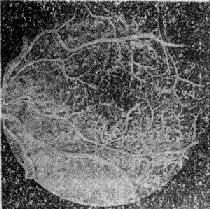

图12-11 糠尿病性视网膜病变 (三)治疗 早期用饮食及药物控制糖尿病.每年定期作眼底荧光血管造影,对增殖型早期应采用激光凝固术治疗病变区,或采用广泛视网膜光凝术。对玻璃体出血引起混浊和机化,可试行玻璃体切割术。